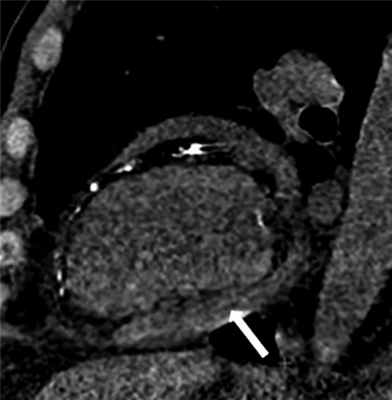

08.05.2019 пациент был вновь госпитализирован в стационар для обследования и определения дальнейшей тактики ведения. При физикальном обследовании отмечено наличие отеков нижних конечностей. По данным КТ органов грудной клетки выявлен компрессионный ателектаз заднебазальных отделов правого легкого, субсегментарные ателектазы язычковых и среднедолевых сегментов. Двусторонний гидроторакс, больше выраженный справа. Неоднородное утолщение висцерального и париетального листков перикарда до 4—5 мм (рис. 1) с выпотом в полость перикарда и сепарацией до 28 мм. Асцит.

Рис. 1. МСКТ органов грудной клетки. Неоднородное утолщение висцерального и париетального листков перикарда до 4—5 мм (указано стрелкой).